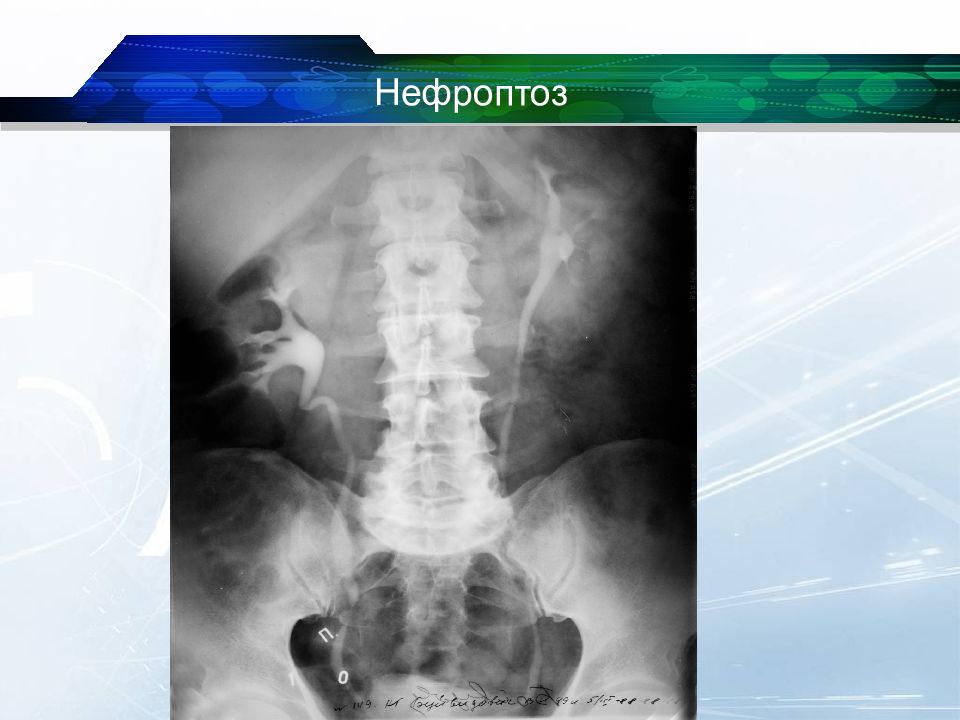

Экскреторная урография при нефроптозе: диагностические изображения